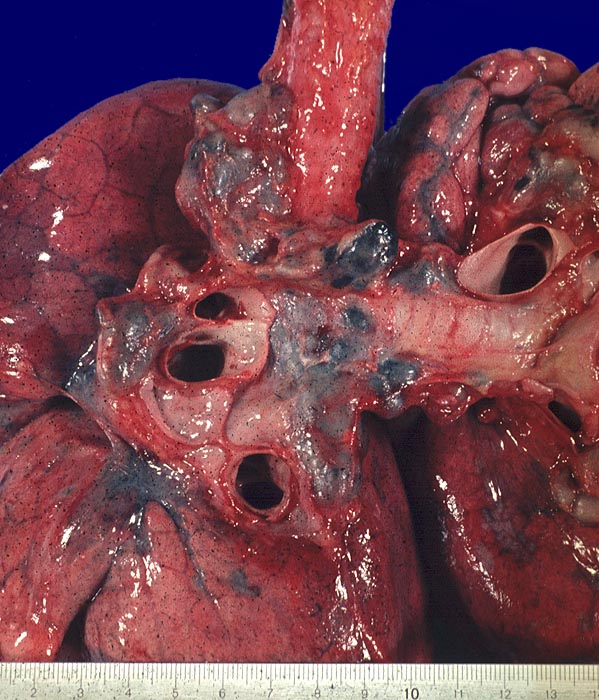

Hiläre Lymphadenopathie bei Sarkoidose

Lymphknoten, Lunge

Die hilären und paratrachealen Lymphknoten sind vergrössert und schiefergrau gefärbt.